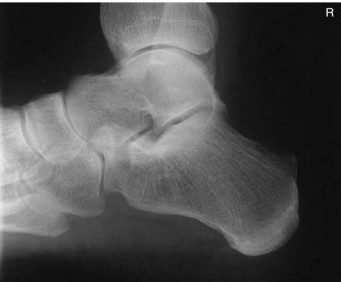

Discuss the correct anatomy demonstrated on this image

entire calcaneus should be seen from tuberosity posteriorly to talocalcaneal joint anteriorly

What is in profile on this image?

susentaculum tali is in profile medially

What indicates on this image that the CR angle was correct?

open talocalcaneal joint space

What is the correct centering point for this calcaneus projection?

1 inch (2.5 cm) inferior to medial malleolus

What anatomy is correctly demonstrated on this lateral calcaneus

calcaneus demonstrated in profile with talus and distal tibfib demonstrated superior and navicular and open joint space of the calcaneus and cuboid demonstrated distally

On this lateral calcaneus image, what indicates no rotation?

superimposed superior parts of the talus, open talocalcaneal joint, lateral malleolus superimposed over posterior half of the tibia and talus. Tarsal sinus and calcaneocuboid joint space should appear open